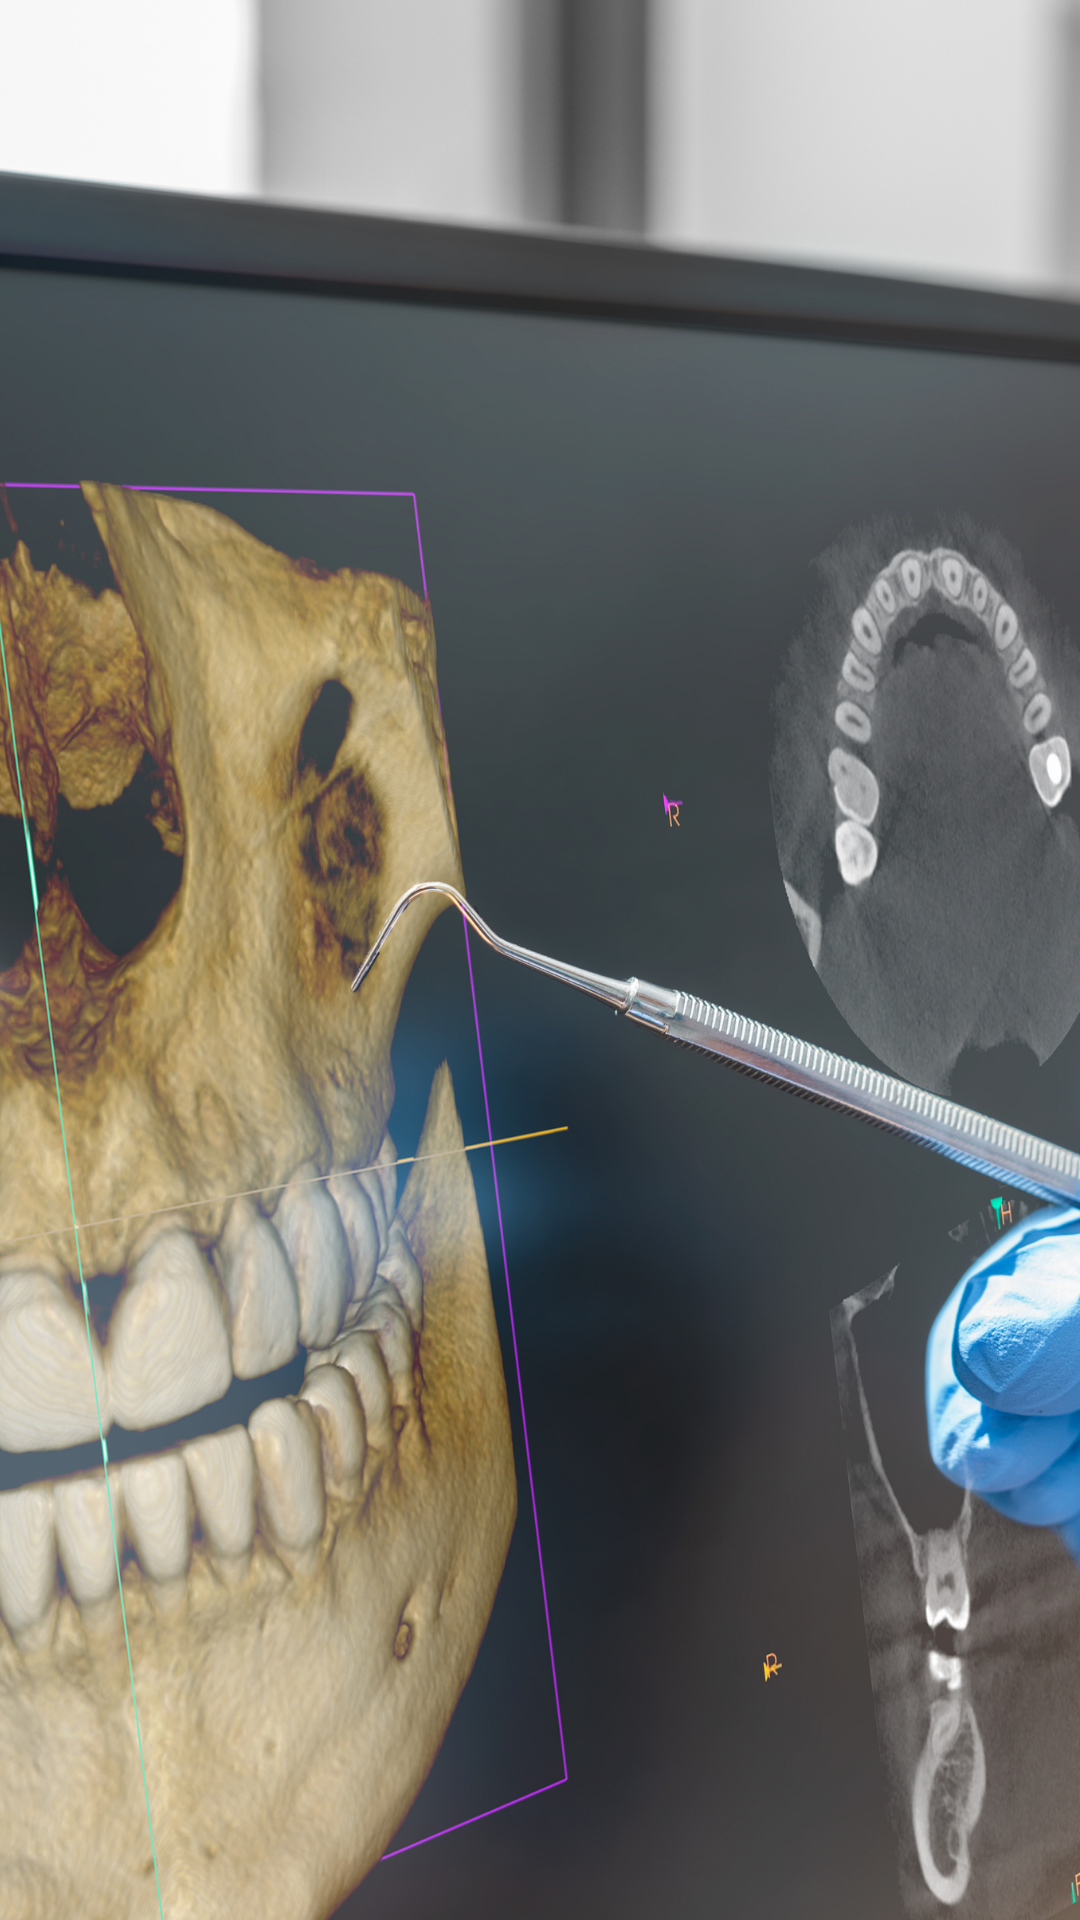

¿Necesitas imágenes tridimensionales precisas? Nuestras tomografías 3D te brindan diagnósticos milimétricos para planificación de tratamientos.